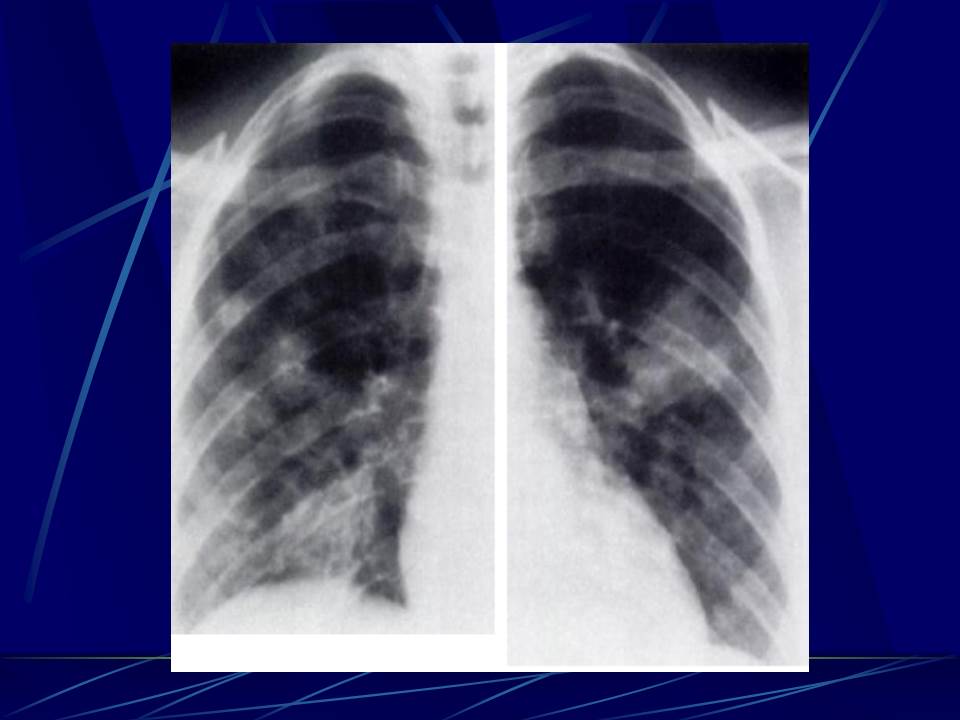

肺部真菌感染影像学分析